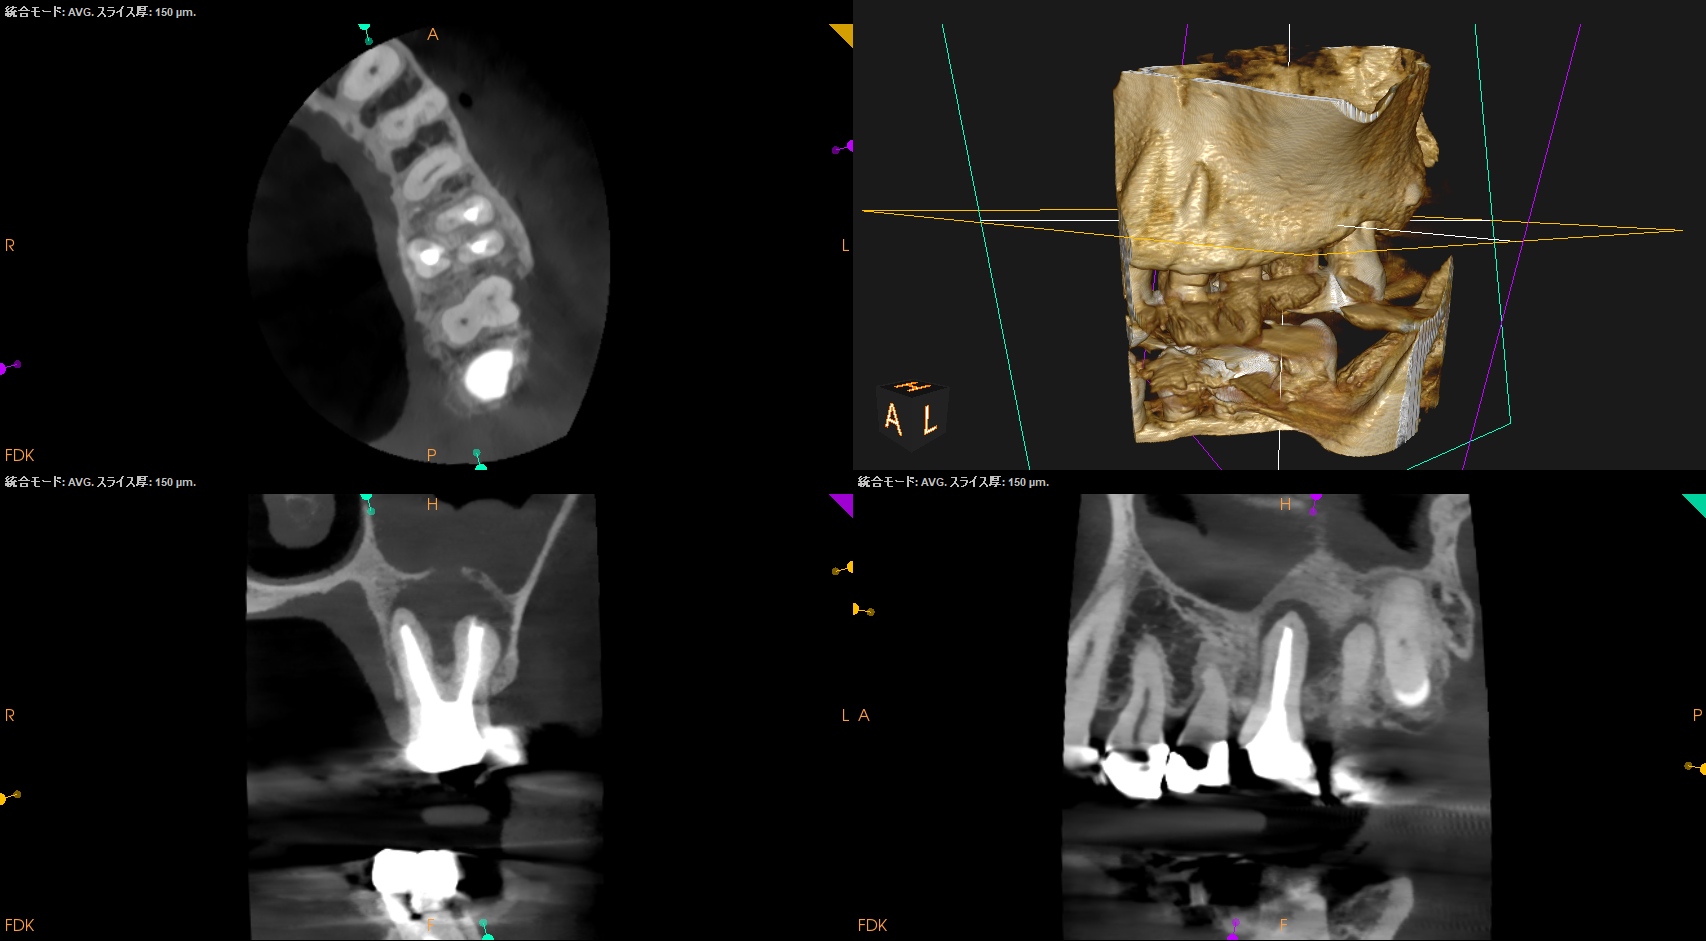

#14 Re-RCT(2023.6.20)

MB,DB,Pの3根全てに病変がある。

#14 Re-RCT 1yr recall(2024.6.10)

1年前よりも状況がひどくなる。

MB,DB,Pの3根同時の根切が必要であったので、

Flapを開けてMB,DBを短く切断してその上でIntentional Replantationを行うと言う治療計画にした。

#14 MB,DB Apicoectomy→Intentional Replantation(2024.6.21)

抜歯作業中に、私は気づかないうちにApico-marginal deffectを人為的に作成してしまっていたようだ。

#14 Intentional Replantation 1yr recall(2025.6.6)

上顎洞炎は治癒し、Pの歯槽骨はかなり回復したがMB,DBは口腔内に歯根が出てしまっている。